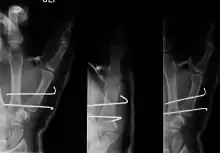

- For Bennett fractures where there is between 1 mm and 3 mm of displacement at the trapeziometacarpal joint, closed reduction and percutaneous pin fixation (CRPP) with Kirschner wires is often sufficient to ensure a satisfactory functional outcome. The wires are not employed to connect the two fracture fragments together, but rather to secure the first or second metacarpal to the trapezium.

Regardless of which approach is employed (nonsurgical, CRPP, or ORIF), immobilization in a cast or thumb spica splint is required for four to six weeks.